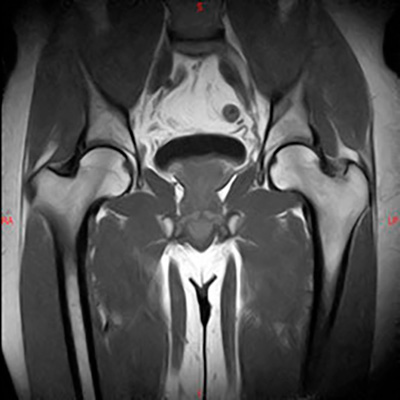

Es el estudio de estructuras anatómicas compuestas por huesos, musculatura, tendones, cartílago etc.

En exploraciones de miembros inferiores, el paciente es colocado en la camilla boca arriba y entran primero los pies, de tal manera que la cabeza queda fuera del gantry, minimizando así la sensación de claustrofobia. Las exploraciones osteoarticulares suelen durar unos 15-20 minutos.

Ejemplos